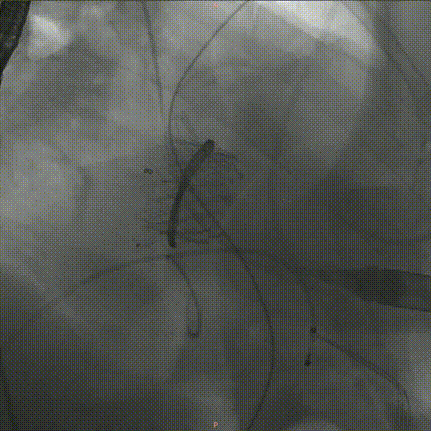

2.在成功建立标准心尖通道并使用六边形缝合方式固定穿刺口后,为了更清晰地显影左心室与左心房结构,术中调整至颅侧右前斜位角度进行操作。造影检查评估二尖瓣反流情况(图D)、左心室形态及瓣环结构。

图D:术中造影提示二尖瓣严重反流

4.随后,沿导丝将输送系统以逆行方式经心尖途径通过二尖瓣成形环推进至左心房。通过回撤输送系统的外鞘,释放出设计用于贴合D形二尖瓣瓣环的心房裙边,该裙边在TEE和造影的引导下精确覆盖于原瓣环及成形环之上,而瓣膜的心室部分仍部分保留在鞘管中。